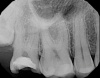

Fig 2. Case 1: Periapical imaging of the maxillary right (Fig 2) and mandibular right (Fig 3) quadrants initially showed no obvious pathology, aside from the horizontally impacted tooth No. 32. Secondary imaging following successful relief of pain after administration of an inferior alveolar nerve block revealed pre-eruptive intracoronal resorption in tooth No. 32 with resultant symptomatic irreversible pulpitis as the likely source of pain (Fig 4).

Figiure 2

Although the patient's chief complaint was consistent with a degenerative pulpitis, the clinical and radiographic examination was initially unremarkable. All teeth in the maxillary and mandibular right quadrants were normally responsive to pulp sensitivity testing, and they were neither percussion nor palpation sensitive. Neither swelling nor sinus tracts were present, and the periodontal examination revealed normal probing depths and lack of mobility throughout the quadrant. Initial periapical radiographs revealed normal PDL spaces surrounding teeth Nos. 30 and 31, as well as a horizontally impacted No. 32 with a radiolucency within the crown in close proximity to the distal root surface of No. 31 (Figure 2 and Figure 3). Because the reported pain was severe, and in an effort to not only diagnose the issue but also offer some respite from the severe pain the patient was experiencing, an inferior alveolar nerve block was administered using 3.4 cc 0.5% bupivacaine with 1:200,000 epinephrine. Within 5 minutes of administration, the patient reported complete resolution of his pain.

Given the confirmation of a likely odontogenic source of pathology since pain was relieved by the block anesthesia, secondary periapical imaging was taken, which showed intracoronal resorption in the unerupted tooth No. 32 (Figure 4). Because of the visualizable pathology and signs and symptoms consistent with a symptomatic irreversible pulpitis, the patient was referred to an oral and maxillofacial surgeon for extraction of tooth No. 32. The patient reported complete resolution of symptoms following extraction of the affected tooth. Communication from the oral surgeon confirmed the diagnosis of intracoronal resorption on tooth No. 32.